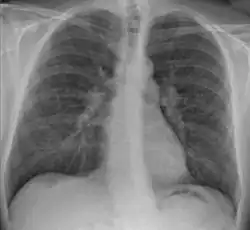

![]() Røntgenbillede med typiske forandringer i lungevæv (markeret) som følge af sarkoidose. | |